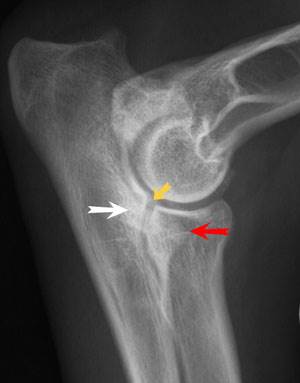

Дисплазия локтевых суставов (ДЛС) часто свойственна таким породам, как лабрадор-ретривер, бернский зенненхунд, немецкая овчарка, золотистый ретривер, ротвейлер, веймаранер и мастиф, но риск заболевания существует у собак и других крупных пород. Эта предрасположенность объясняется тем, что у крупных собак сустав состоит из многих костей и полностью формируется только к концу роста собаки: у крупных собак около 1,5 лет, у очень крупных – около 2 лет.

Если к наследственному дефекту в период роста организма добавляется еще и травма, риск развития различных типов дисплазии локтевого сустава очень велик (фрагментация крючковидного отростка, фрагментация медиального венечного отростка (внутренний венечный отросток), расслаивающий остеохондрит, медиальный компартмент синдром).

При появлении хромоты на грудную конечность, особенно у молодых животных, следует срочно обратиться к ветеринарному врачу. Если дисплазия локтевого сустава связана с одной из перечисленных патологий, правильные действия врача и владельца животного – это единственное средство, чтобы не допустить развития артроза у собаки. Если образовалась так называемая «суставная мышь» (фрагмент, свободно лежащий в суставной щели), то необходима операция. Сегодня эта операция выполняется специалистами с помощью артроскопии, с минимальным повреждением тканей.